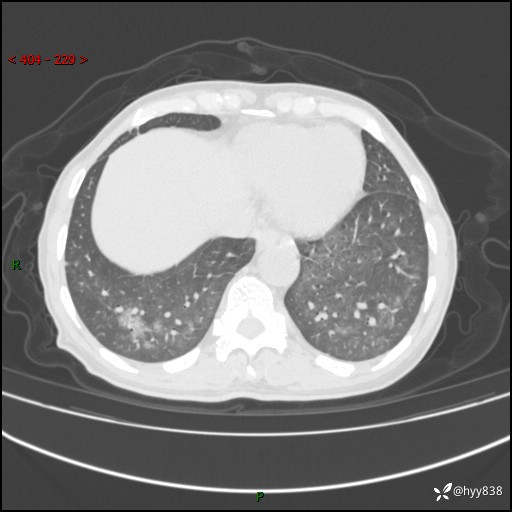

辅助检查:CT

胸部CT平扫

不是讨论肺部结节